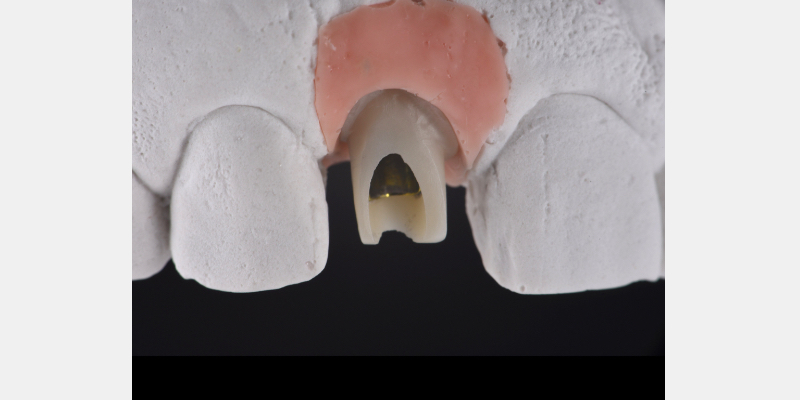

Here is a simple, step-by-step technique for fabricating a silicone jig to avoid excess cement in a cement-retained implant-supported restoration. It can be applied to a single crown or to an implant-supported cement-retained bridge.